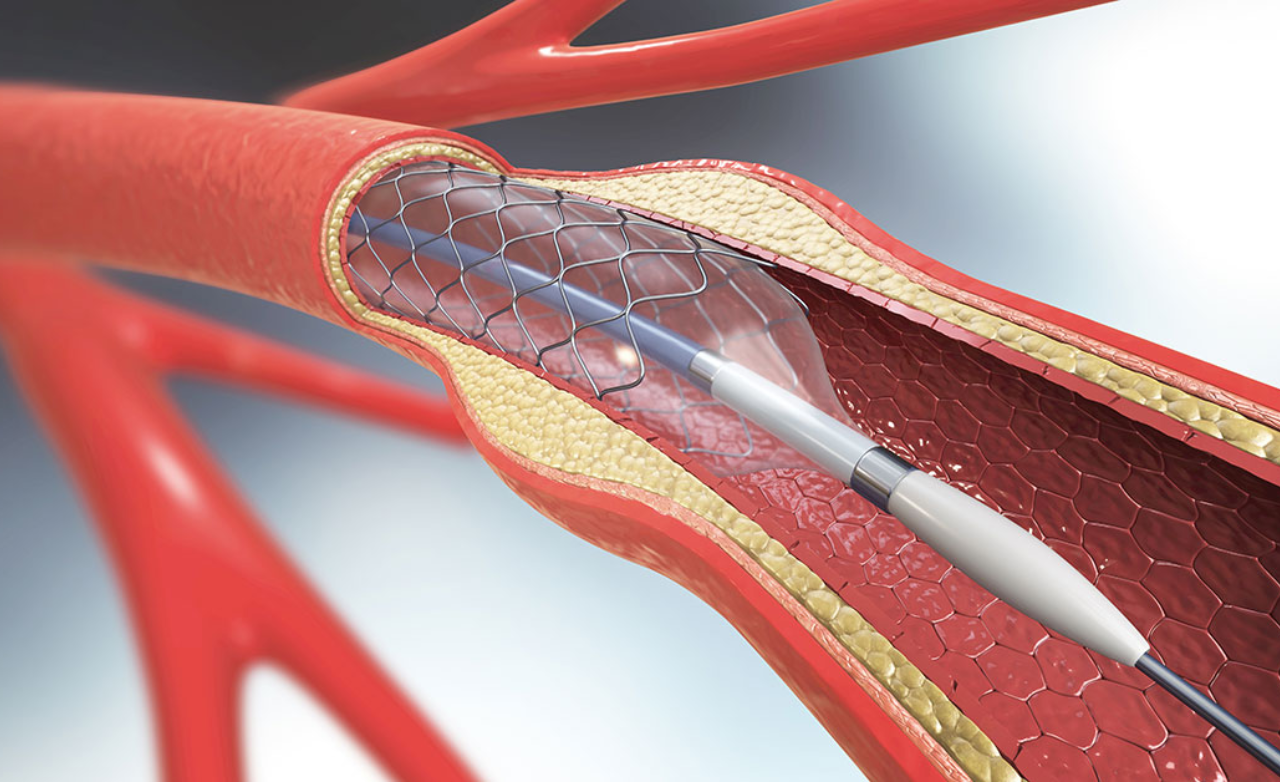

Carotid and vertebral artery stenting is a minimally invasive procedure used to treat narrowing of arteries supplying blood to the brain, which significantly increases stroke risk. Symptoms may include dizziness, weakness, or transient vision loss.

A stent is placed to widen the artery, restore smooth blood flow, prevent future strokes, and improve long-term brain circulation safely.

Intracranial stenting treats severe narrowing of arteries located within the brain that can cause recurrent strokes or reduced cerebral blood flow.

The procedure widens the affected vessel, improves circulation, and lowers the risk of further ischemic events in carefully selected patients.

Opens narrowed arteries supplying the brain, improving blood flow and reducing stroke risk through a precise, minimally invasive procedure.